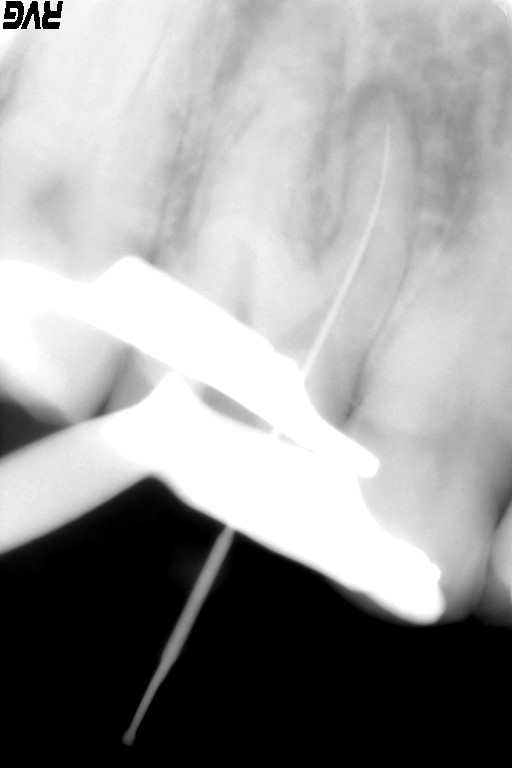

根管の先、根尖を確認するためにファイルを入れた状態でレントゲンを撮り、根管の長さや根尖孔の太さや状態を確認しています。

根尖までの長さや根尖孔の太さを確認するためにファイルを入れてレントゲン撮影を行います。